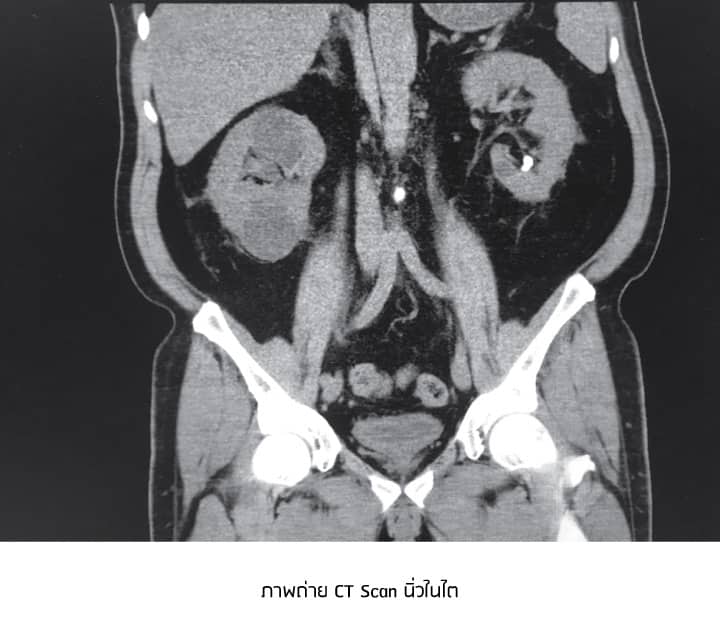

การวินิจฉัย ทำได้โดยการตรวจเลือด ตรวจปัสสาวะ และการตรวจทางรังสีวินิจฉัยด้วยเครื่องเอกซเรย์คอมพิวเตอร์ช่องท้อง หรือที่เรียกว่าการทำซีทีสแกน (CT Scan)